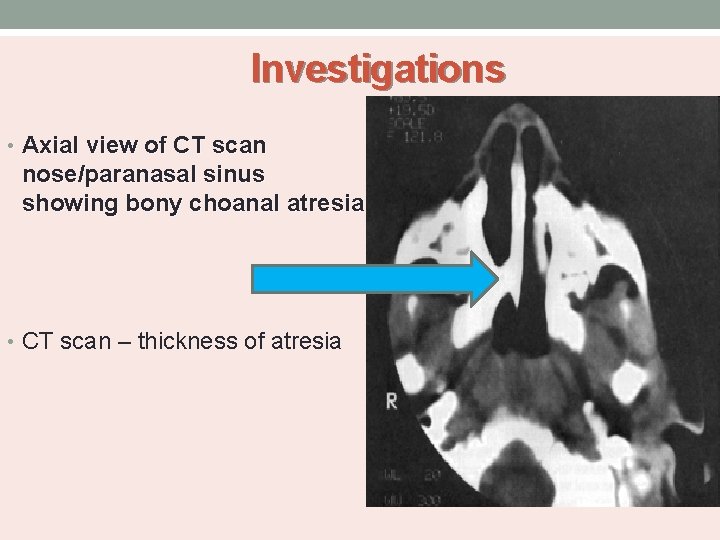

Investigations • Rhinography - administration of radiopaque dye into the nasal cavity. • CT scan -Confirm the diagnosis of choanal atresia (unilateral or bilateral). -Evaluate choanal atresia (vomer bone width). -Exclude other possible nasal sites of obstruction. -Determine the degree of bony, membranous, or mixed atresia. -Other abnormalities in the nasal cavity and nasopharynx.

Investigations • Axial view of CT scan nose/paranasal sinus showing bony choanal atresia • CT scan – thickness of atresia